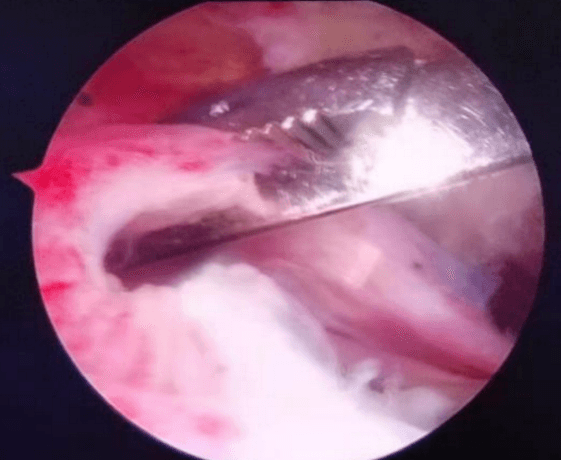

七年前從零出發(fā),從無(wú)到有,從有到精,李鵬主任帶領(lǐng)團(tuán)隊(duì)人員,先后在西安、上海、北京、廣州等獨(dú)家頂級(jí)關(guān)節(jié)運(yùn)動(dòng)醫(yī)學(xué)中心學(xué)習(xí),屢次開(kāi)創(chuàng)引進(jìn)新技術(shù),填補(bǔ)我院多項(xiàng)技術(shù)空白。先后開(kāi)展了首例膝關(guān)節(jié)鏡、首例肩關(guān)節(jié)鏡手術(shù),首例踝關(guān)節(jié)鏡手術(shù),首例肘關(guān)節(jié)鏡手術(shù),首例髖關(guān)節(jié)鏡手術(shù),完成了技術(shù)要求高、難度大的肩袖損傷修復(fù)手術(shù)、肩關(guān)節(jié)復(fù)發(fā)性脫位、BanKart損傷修復(fù)手術(shù),后交叉韌帶下止點(diǎn)骨折、膝關(guān)節(jié)多發(fā)韌帶損傷重建手術(shù)等,標(biāo)志著我院在骨關(guān)節(jié)運(yùn)動(dòng)醫(yī)學(xué)專業(yè)及關(guān)節(jié)鏡微創(chuàng)手術(shù)技術(shù)的顯著提升。

當(dāng)前越來(lái)越多的人意識(shí)到健康的身體是1,其他的都是0,有了這個(gè)1,其他的0才有了存在的意義和價(jià)值。所以越來(lái)越多的人開(kāi)始關(guān)注運(yùn)動(dòng)、開(kāi)始參與運(yùn)動(dòng)。然而,如何正確的運(yùn)動(dòng),如何預(yù)防運(yùn)動(dòng)損傷,如何在運(yùn)動(dòng)損傷后得到專業(yè)的治療,如何在運(yùn)動(dòng)損傷治療后得到快速的康復(fù)等,就需要一個(gè)專業(yè)的學(xué)科來(lái)解決這些問(wèn)題。這個(gè)學(xué)科就是運(yùn)動(dòng)醫(yī)學(xué)。運(yùn)動(dòng)醫(yī)學(xué)是一門新興的醫(yī)學(xué)科目,是醫(yī)學(xué)與關(guān)節(jié)運(yùn)動(dòng)相結(jié)合的綜合性應(yīng)用科學(xué)。主要是研究與關(guān)節(jié)運(yùn)動(dòng)有關(guān)的醫(yī)學(xué)問(wèn)題,包括關(guān)節(jié)的慢性勞損和急慢性損傷。范圍涵蓋了膝關(guān)節(jié)、肩關(guān)節(jié)、髖關(guān)節(jié)、踝關(guān)節(jié)及肘關(guān)節(jié)。膝關(guān)節(jié)骨關(guān)節(jié)炎、半月板損傷、交叉韌帶損傷、髕骨脫位、游離體(滑膜軟骨瘤?。?、肩關(guān)節(jié)凍結(jié)肩、肩袖損傷、肩峰撞擊征、肩關(guān)節(jié)復(fù)發(fā)性脫位、肩關(guān)節(jié)SLAP損傷、肘關(guān)節(jié)骨關(guān)節(jié)炎、踝關(guān)節(jié)撞擊癥、踝關(guān)節(jié)不穩(wěn)以及臀肌攣縮癥、髖股撞擊癥等,這些疾病都可以到運(yùn)動(dòng)醫(yī)學(xué)科就診。運(yùn)動(dòng)醫(yī)學(xué)能夠有效的、針對(duì)性的解決各類急慢性關(guān)節(jié)疼痛。主要是利用關(guān)節(jié)鏡微創(chuàng)技術(shù),能夠快速有效的緩解關(guān)節(jié)疼痛,具有創(chuàng)傷小、恢復(fù)快、效果顯著等優(yōu)點(diǎn)。

微創(chuàng)、精準(zhǔn)、快速康復(fù)已成為骨科疾病與創(chuàng)傷治療的必然趨勢(shì)。我院骨關(guān)節(jié)及運(yùn)動(dòng)醫(yī)學(xué)亞??剖俏以和饪撇≡褐攸c(diǎn)發(fā)展的亞專科方向。李鵬作為專業(yè)團(tuán)隊(duì)的負(fù)責(zé)人,科室目前配備有全套進(jìn)口關(guān)節(jié)鏡手術(shù)設(shè)備,高清顯像系統(tǒng),全體醫(yī)護(hù)團(tuán)結(jié)協(xié)作,嚴(yán)謹(jǐn)細(xì)致,踏實(shí)前行,以精湛的醫(yī)療技術(shù)和優(yōu)質(zhì)的護(hù)理服務(wù),為患者提供了優(yōu)質(zhì)醫(yī)療服務(wù),贏得了廣大患者的信任和肯定。

肩袖損傷手術(shù)

擅長(zhǎng)治療各種骨關(guān)節(jié)外傷、骨關(guān)節(jié)疾病。手術(shù)方面擅長(zhǎng)髖、膝關(guān)節(jié)置換術(shù)、膝關(guān)節(jié)單髁置換術(shù)、脛骨高位截骨術(shù)、股骨頸骨折及轉(zhuǎn)子間骨折等手術(shù)。富血小板血漿(PRP)治療骨關(guān)節(jié)炎。擅長(zhǎng)關(guān)節(jié)鏡下膝關(guān)節(jié)交叉韌帶重建、半月板損傷縫合、髕骨脫位、肩袖修補(bǔ),肩峰撞擊征、鈣化性肌腱炎,肱二頭肌長(zhǎng)頭腱炎,髖關(guān)節(jié)盂唇損傷、髖關(guān)節(jié)撞擊征、踝關(guān)節(jié)不穩(wěn)、踝關(guān)節(jié)韌帶損傷、肩關(guān)節(jié)不穩(wěn)、肩周炎、各類關(guān)節(jié)內(nèi)骨折、關(guān)節(jié)脫位的手術(shù)治療。